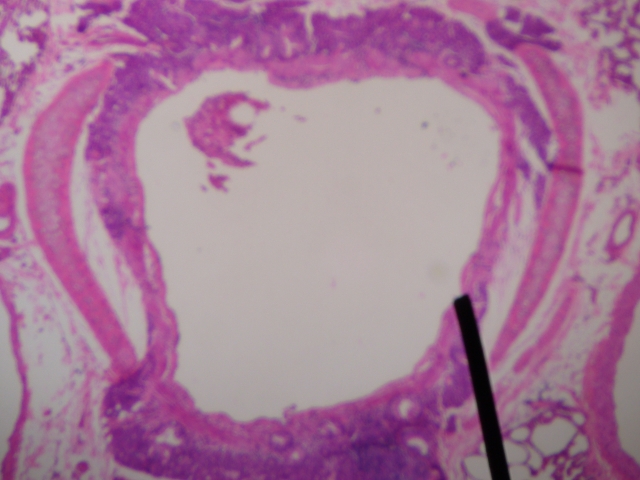

La bronchite acuta è un'infiammazione delle grandi vie aeree che si presenta in modo repentino con la comparsa dei sintomi e che si risolve in tempi brevi.La diagnosi si esegue in base ai sintomi e la malattia evolve senza necessità di grandi interventi farmacologici.

La bronchite acuta è una patologia di tipo infiammatorio che colpisce i bronchi e talvolta la trachea. Si manifesta con sintomi che compaiono rapidamente in un paziente sano e che sono per lo più legati ad infezioni soprattutto virali (nella forma acuta infettiva), o ad agenti irritanti inalati (nella forma irritativa).